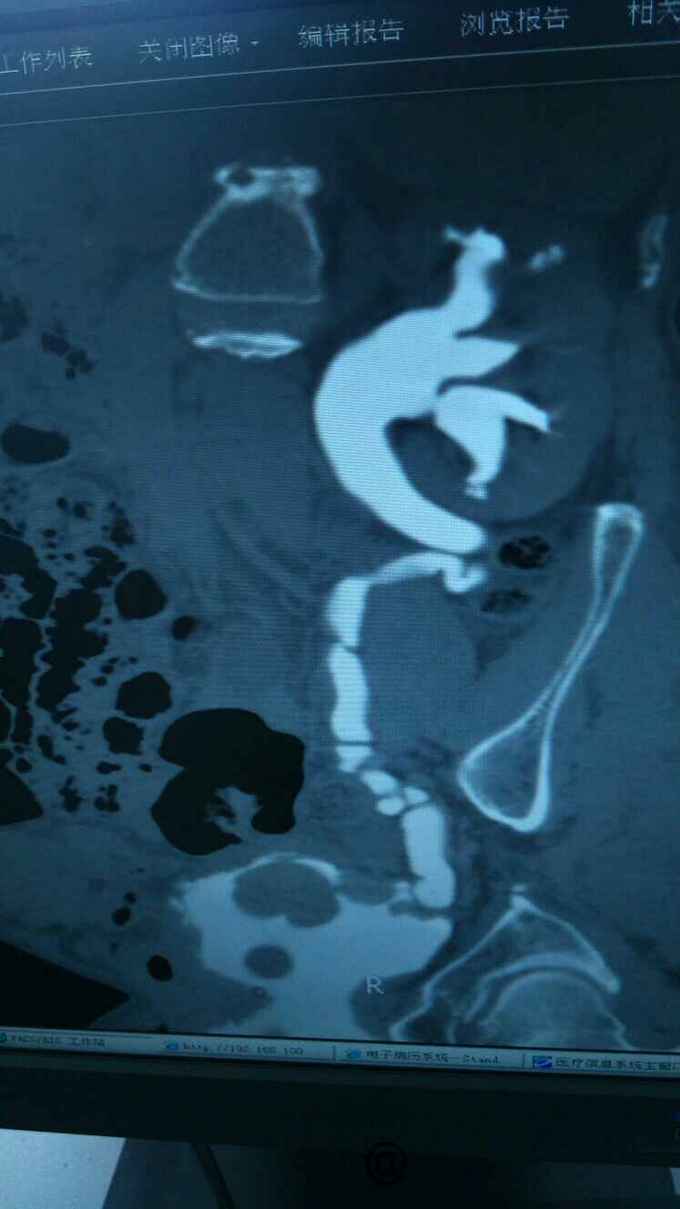

查膀胱镜发现后尿道狭窄,无法进入膀胱。 尿道造影:尿道狭窄,输尿管逆流。嘱咐病人排尿时,膀胱内尿液减少,进入输尿管,肾盂。 肾功能正常。

诊断:尿道狭窄,输尿管逆流 治疗:输尿管镜下探查,见尿道狭窄,膀胱内景清晰,广泛房小梁形成,右侧膀胱后壁可见广口凹陷,输尿管镜置入,可向上探查,实为输尿管,管腔宽大,输尿管镜进出自如,未见占位病变,向膀胱内置入导丝,沿着导丝留置导尿管扩张尿道。